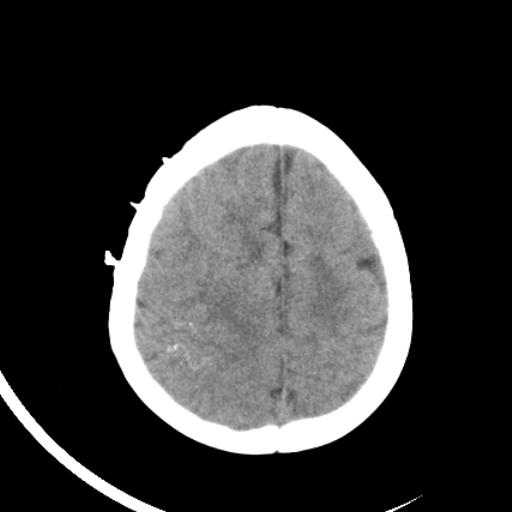

双侧脑室前后角周围白质片状低密度影,双侧侧脑室旁、双顶叶皮层及皮层下多个小原点状钙化灶,不除外torch感染。右顶叶脑回似乎较对侧大,建议mri检查以除外脑发育异常。

考虑:1、巨脑回畸形(皮质明显增厚+脑回明显增宽+白质减少)。

2、torch综合征(室管膜下钙化+白质内及皮髓质交界处多发钙化)。